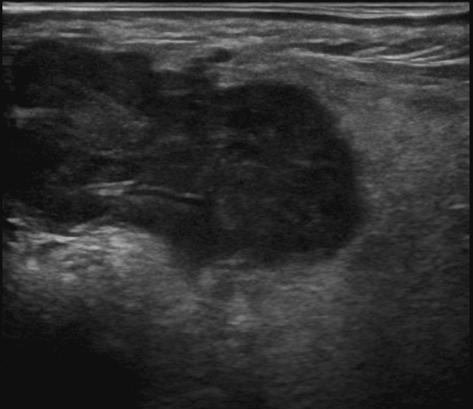

U tuyến nước bọt

U tuyến nước bọt - Ảnh 5

» Thông tin: Nam giới – 72 tuổi.

» Lâm sàng: Khối vùng mang tai.

# Ung thư biểu mô tuyến (Adenocarcinoma).